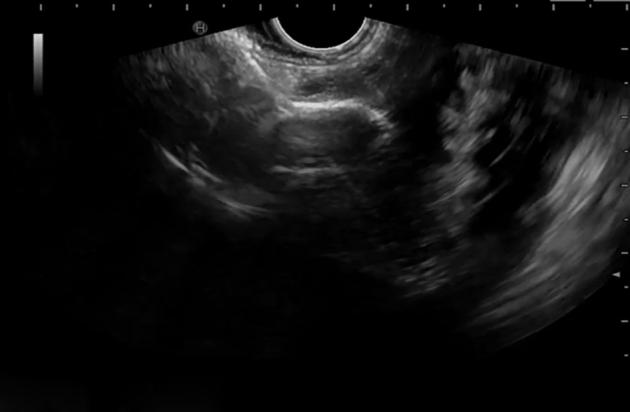

一名患有神经功能障碍且需要空肠喂养的男孩,接受内镜超声引导下带管腔对合金属支架的胃空肠吻合术。

Endoscopic ultrasound-guided gastrojejunostomy with lumen-apposing metal stent in a boy with neurological impairment requiring jejunal feeding.

Video 1EUS-guided, LAMS-assisted gastrojejunostomy for re-routing a PEGJ tube in neurologically impaired children.

视频1:超声内镜引导下,使用可回收金属支架辅助进行胃空肠造口术,用于重新安置神经功能受损儿童的经皮内镜下胃空肠造瘘管。